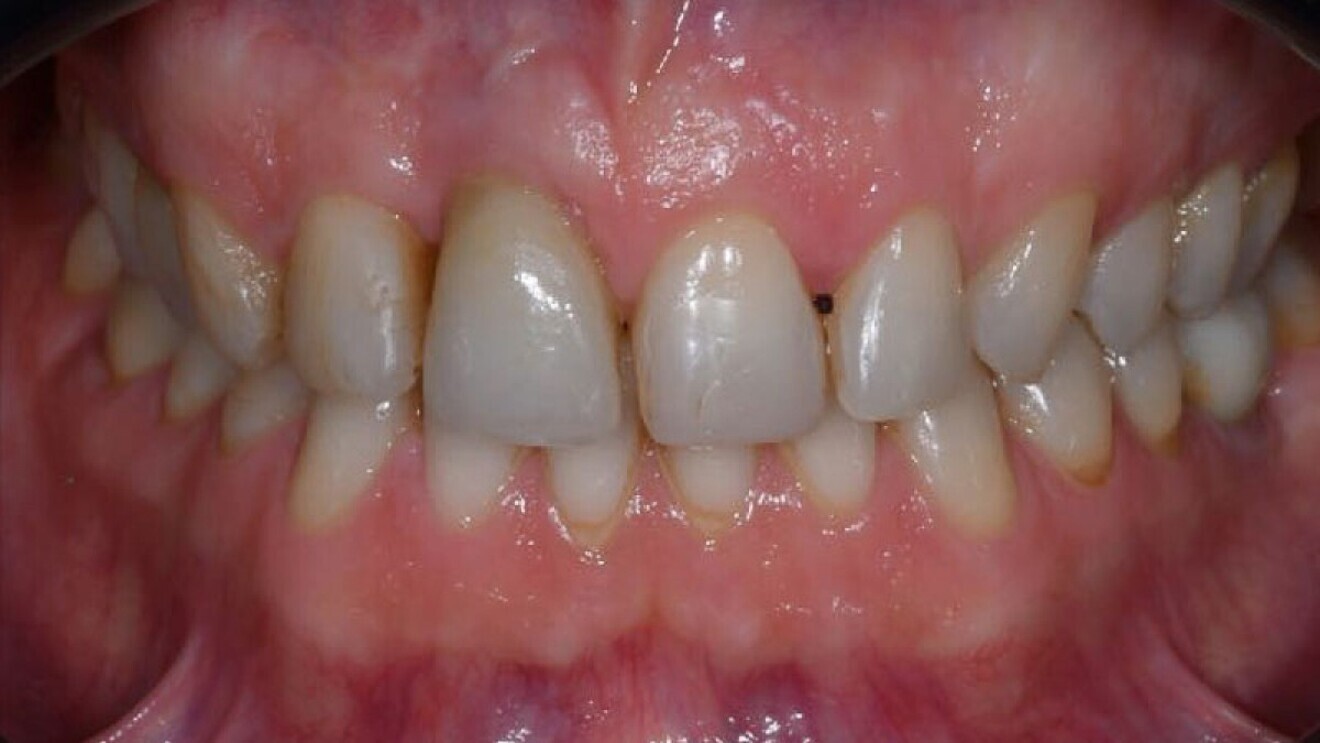

Wanneer de behandelaar de uitvoering van alle vereiste bewegingen heeft beoordeeld, kan hij de aligners aanvragen. Nadat de orthodontische behandeling is voltooid, kan men verdergaan met de restauratieve behandeling, altijd via een volledige digitale workflow (afb. 8, 9).

Afb. 8

Afb. 9